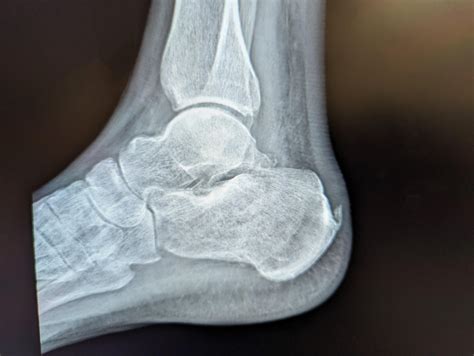

In medical terminology, a "lesion" is simply an area of abnormal tissue. When prefixed with "lytic," it refers to osteolysis, the process of bone resorption or destruction. Put simply, lytic bone lesions occur when cells called osteoclasts break down bone tissue faster than osteoblasts (the cells responsible for bone formation) can replace it. This creates a hole or a "punched-out" appearance in the bone that is clearly visible on imaging studies.

The appearance of these lesions can vary significantly depending on the underlying cause. Some may look like small, well-defined holes, while others might have irregular, "moth-eaten" edges. Because they weaken the bone structure, they increase the risk of pathological fractures—breaks that occur even with minimal trauma or stress on the bone.

Radiologists use specific features to estimate whether a lesion is likely benign or malignant. While imaging alone is rarely definitive, it provides essential clues for the clinical team.